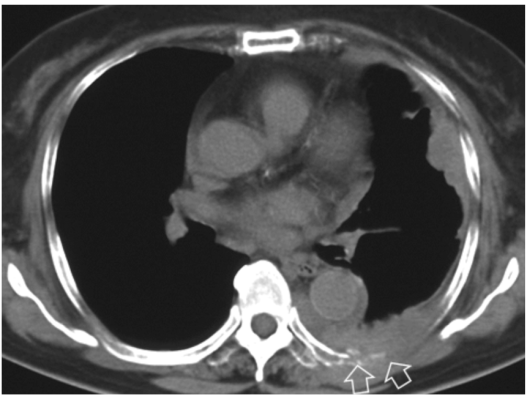

胸膜中皮腫(T4):切除不可能な胸壁浸潤

背部の胸膜腫瘍は、胸膜下脂肪織を超え、肋骨を浸潤し、胸壁に高度に浸潤している(矢印)。